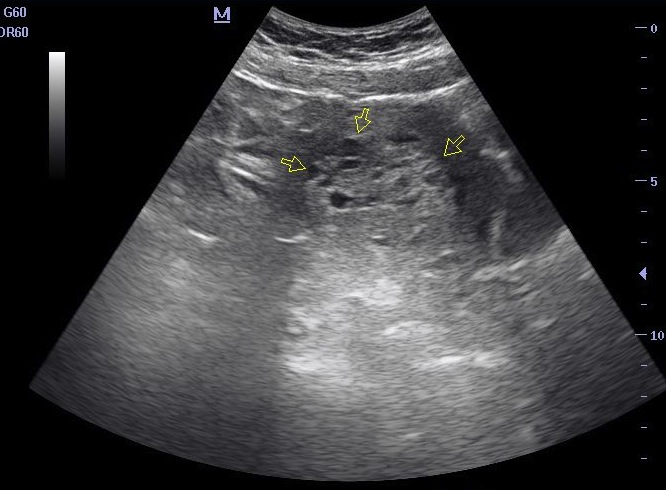

pregnancy molar ultrasound mole uterus complete enlarged trophoblastic disease transabdominal gestational pelvis echogenic endometrial arrow cystic areas multiple within revealing